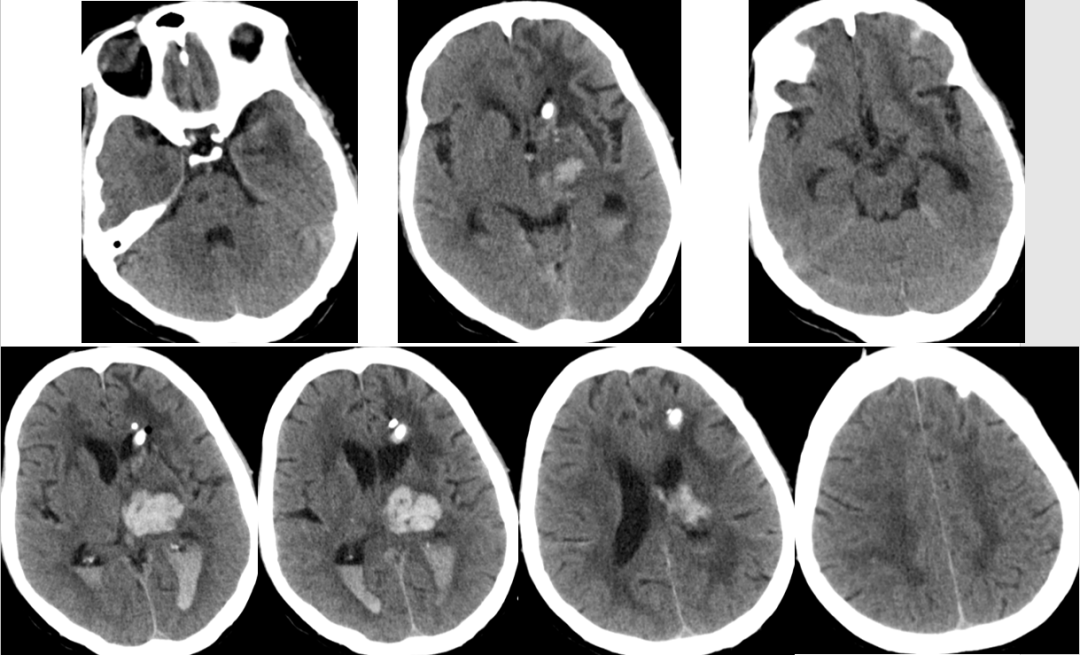

2014-11-27 CT

分析

腰大池引流白天50ml,降低引流管高度,在半个小时左右突然100多ml,颜色由淡红转为鲜红色,继而意识障碍加重有昏睡转为浅昏迷,收缩压升高到200mmHg。

非高颅压脑疝!

加强脱水!

患者1小时后清醒。

2014-12-2 CT

患者生命征平稳,精神可,一般情况好。

神经系统检查:神清清醒,有遵嘱动作,反应稍迟钝,左侧瞳孔2.5mm,右侧瞳孔3mmm,对光反射均稍迟钝,右上肢肌力粗测约2级,右下肢肌力粗测约3级,肌张力正常,左侧肢体肌力及肌张力粗测正常,右侧巴氏征阳性,余神经系统查体不能配合。

转院康复治疗。